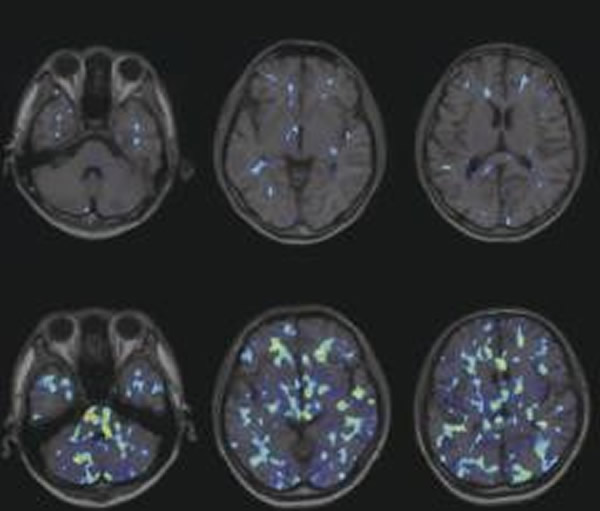

据日本《东京新闻》11月27日消息,日本浜松医科大学研究小组27日在美国医学专业杂志上发表的文章称,他们通过研究发现,患有自闭症的人主要是由于担负大脑免疫功能的小神经胶质细胞过于频繁活动所致。

据悉,为了解小神经胶质细胞的活动情况,研究小组专门在被调查者的头部放置了头部专用阳电子放射断层摄影(PET),并分别对18至30岁之间未进行药物治疗的20名自闭症患者,以及20名非自闭症患者进行了调查。结果显示,与正常人相比,患有自闭症的人,其小脑以及脑干等部位的小神经胶质细胞的活动比较频繁,而小脑与脑干又恰巧都是被认为与患自闭症有关的部位。